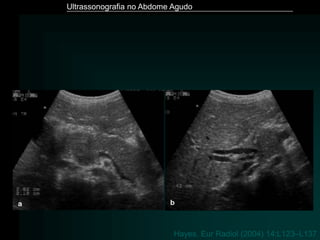

Pancreatite Aguda

• Exame de imagem de eleição - Tomografia Computadorizada

• ULTRASSONOGRAFIA

– Limitação - distensão gasosa

– Detecção de litíase biliar

– Aumento volumétrico

– Hipoecogenicidade difusa ou focal

– Dilatação do Wirsung

– Perda de definição dos limites

– Áreas hiperecogênicas – hemorragia

– Coleções – às vezes o único achado

Ultrassonografia no Abdome Agudo

Hayes. Eur Radiol (2004) 14:L123–L137